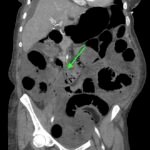

Recognition of the whirl sign on computed tomography (CT) imaging can improve patient outcomes in those presenting with small bowel obstruction (SBO). In the case highlighted in this report, a 40-year-old woman with a remote history of gastric bypass presented to the emergency department (ED) with four hours of abdominal pain and vomiting. Findings on the initial CT of the abdomen and pelvis were suggestive of SBO with a whirl sign pattern. The whirl sign occurs after the bowel rotates around the mesentery, leading to a visual “whirl” of mesenteric vessels. Unfortunately, despite prompt diagnosis, the patient developed an ischemic bowel and ultimately sustained a prolonged hospital course requiring multiple bowel resections. ED providers should familiarize themselves with the whirl sign because its presence in patients with SBO increases the likelihood of ischemia. These patients should have urgent surgical consultation to decrease overall morbidity and mortality.

Whirl sign, small bowel obstruction, gastric bypass, internal hernia.